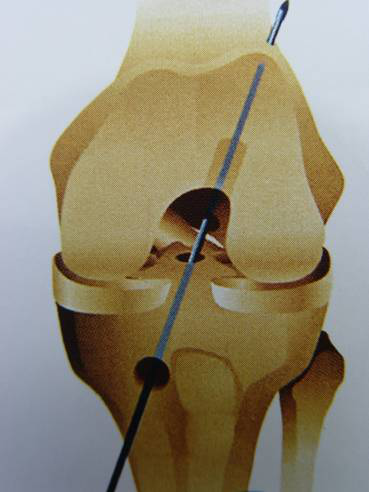

1.準(zhǔn)確定位,建立骨隧道。

脛骨點(diǎn)選取

股骨點(diǎn)